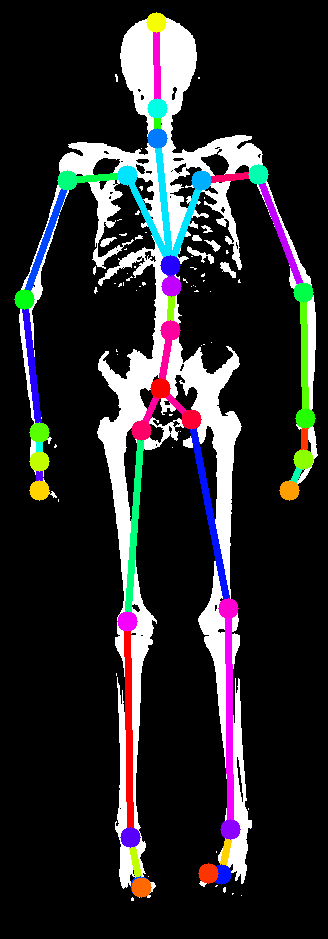

Many model-based human pose estimation methods rely on fitting projected 3D joints to 2D landmarks. Landmark detection must be automated as we fit thousands of DXA images. Existing landmark detectors, of course, do not work with DXA imagery. Consequently, we train a landmark detector for skeleton binary masks . To do so, we generate synthetic training data using an initial skeleton mesh similar to the one from Anatomy Transfer (AT) [1]. We rig the skeleton so that we can control it with the STAR shape and pose parameters (see Sup. Mat. for details), and define 29 landmarks on the skeleton mesh, , that are in correspondence with the 3D joints of the STAR model. This allows us to generate skeletons of different shapes in lying down poses, which we render as binary images with the projected landmarks, giving us paired training data.

To bridge the domain gap between the synthetic silhouettes and the DXA segmentations, we augment the data by eroding and partially masking the rendered skeleton silhouettes, while keeping the landmarks fixed. From the synthetic silhouettes of the skeleton, we train the landmark detector using a stacked hourglass network [22]. In Sup. Mat., we provide the details and evaluation of this network.

In order to register the skin and skeleton models to the DXA scans, we need 2D landmarks on the scans. In this section we explain how we generate the synthetic dataset (Sec. A.1, Sec. A.2) to train a 2D landmark predictor from DXA skeleton silhouettes (Sec. A.3) and evaluate the prediction (Sec. A.4). The 2D landmark prediction from DXA silhouette is illustrated in Fig. 6.

We define 29 landmarks on the skeleton mesh (Fig. 7). The first 24 correspond to the closest vertex to the STAR joint locations. Additionally we select the tip of the head, fingers and feet. We denote these initial landmarks or if we make explicit the mesh on which the landmarks are defined.

In our skeleton model, we manually define 21 groups of bones that belong to the same anatomic part, and define the interfaces between these parts. In Fig. 10 we show the different parts with color codes, their interfaces, as well as the 3D landmarks defined on the bones.